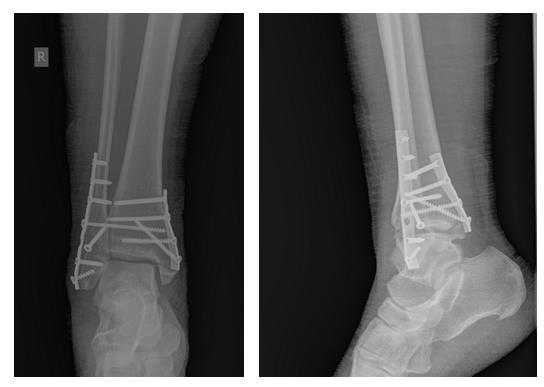

Клинический случай 1. Перелом обеих лодыжек с подвывихом стопы кнаружи.

44 В2-2

Пациентка Т. 80 лет. Травма за 3 недели до обращения, получила перелом обеих лодыжек правой голени со смещением, подвывихом стопы кнаружи. Обратилась в РТП, выполнена рентгенография, наложена гипсовая повязка. В связи с сохраняющимся выраженным отёком и болевым синдромом обратилась в клинику К+31.

На рентгенограммах в гипсе определяется значительный подвывих таранной кости кнаружи, консолидирующийся перелом нижней трети малоберцовой кости.

В день обращения пациентка послоностью обследована, проведено оперативное лечение, открытая репозиция, остеосинтез перелома нижней трети малоберцовой кости пластиной, внутренней лодыжки винтом, внутренняя лодыжка дополнительно фиксирована анкерным фиксатором.

На контрольных рентгенограммах после операции положение отломков, металлофиксаторов правильное, подвывих таранной кости устранён.

Пациентка выписана на 2 сутки после операции на амбулаторное долечивание.